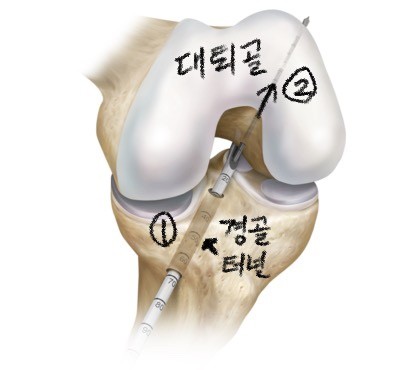

- 경경골 술기 (trans-tibial technique)

1. 먼저 경골을 뚫어 터널을 만든 후,

2. 무릎을 굴곡 시킨 상태에서

3. 이 경골 터널을 이용하여 대퇴골 터널을 만들어

인대를 통과시킨 후 고정하는 방법입니다.

이 방법은 전통적으로 오랫동안 사용되어 왔던 방법인데

처음엔 대퇴골 터널 방향이 11시 방향이었습니다.

이러한 위치를 등장점(isometric point) 라고 부르며

가장 이상적인 포인트라고 여겨졌었는데,

인대의 방향이 너무 수직으로 향하게 되면

회전 불안정성이 생긴다는 것이 밝혀지면서

점차 원래 십자인대의 부착되는 부위를 재건하는 방향으로

십자인대 재건술이 발전했습니다.

최근에는 경경골 술기를 사용하는 경우에도

이전보다 조금 더 비스듬한 방향으로 터널을 만들어

전방 안정성과 회전 안정성을 얻고 있습니다.

(10시 방향)